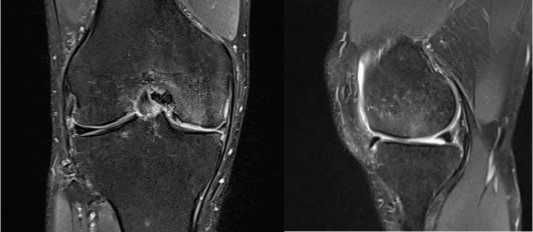

На рентгенографии не выявлено признаков костно-травматической патологии. На МРТ левого коленного сустава от марта 2025 – хрящевой дефект медиальной фасетки надколенника размером 13 мм × 40 мм (Рисунок 3).

Рисунок 3. МРТ дефекта хряща левого надколенника в сагиттальном и аксиальных проекциях

Выполнено МРТ исследование левого коленного сустава для оценки заполненности дефекта хряща надколенника регенератом (Рисунок 6).

Рисунок 6 . МРТ исследование левого коленного сустава и зарастание дефекта хрящевой ткани суставной поверхности надколенника

При клиническом осмотре выявлено ограничение объёма движений с амплитудой сгибания–разгибания от 15° до 100°. Симптомы повреждения латерального мениска – отрицательные, однако с медиальной стороны отмечается болевой синдром при проведении тестов Мак-Мюрррея и Апли; признаков нестабильности коленного сустава, а также локальных проявлений воспаления не обнаружено. По данным рентгенографии признаков костно-травматической патологии не выявлено; определяется умеренное сужение медиальной суставной щели. МРТ-исследование выявило хрящевой дефект медиального мыщелка бедренной кости размерами 25 мм × 20 мм (площадь 5 см2) и разрыв в области заднего рога медиального мениска (Рисунок 7).

Рисунок 7 . Изображения снимков фронтального и сагиттального срезов с демонстрацией дефекта в области медиального мыщелка правой бедренной кости

Рисунок 10. МРТ снимки хрящевой ткани суставной поверхности коленного сустава для выявления участков заращения у пациента с дефектом хряща левой бедренной кости